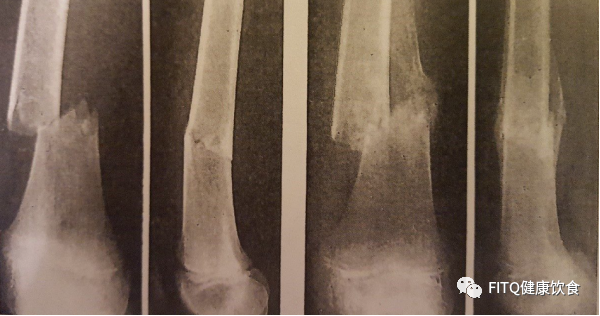

(Liu, et al., 2022 | The Journal of Clinical Investigation) D+Q治疗恢复骨生长和恢复干细胞生长。E)左图为含培养皿的愈伤组织:一个培养皿未经处理(Veh),一个培养皿含有过氧化氢(H2O2)诱导衰老细胞,一个培养皿含有过氧化氢并经过D+Q处理(H2O2 + D+Q)。右图显示D+Q恢复了H2O2/衰老细胞引起的骨生长减少。G)未处理的老年骨中干细胞减少(蓝色),但D+Q处理可恢复(红色)。Liu和他的同事们展示了短期内如何通过使用D+Q治疗来减少衰老细胞来促使老年人骨折愈合。先前的一项研究已经表明,D+Q治疗可以改善年轻和成年小鼠的骨折愈合。总的来说,研究越来越倾向于使用抗衰老剂来改善骨骼健康,包括骨折愈合,目前有一项临床试验对120名老年女性展开使用D+Q治疗法或非塞汀的使用的评估(NCT04313634)。抗衰老剂(Senolytics)不仅在其他老龄化领域带来潜在益处,更多的可能是成为提高老年人骨折愈合良剂的答案。其实我们在许多健康食品店和网上都可以购买到槲皮素(quercetin)和非瑟丁(fisetin)等产品来作为保健品或抗衰老补充剂的组合品,但达沙替尼(dasatinib)就只能作为化疗处方药在专门药店进行购买。如果想要尝试抗衰老剂的朋友们还是建议咨询专业医生后通过正规渠道购买,切勿随意尝试没有通过食品药物监管局的药物噢!本文结论性观点源于美国医学图书馆研究报告(National Library of Medicine),由水母健康团队编译。本文内容仅用于健康知识的学习与交流,不代表水母健康持有该观点。报告材料:Liu, J., Zhang, J., Lin, X., Boyce, B.F., Zhang, H., Xing, L. (2022) Age-associated callus senescent cells produce TGF-β1 that inhibits fracture healing in aged mice. The Journal of Clinical Investigation https://doi.org/10.1172/JCI148073